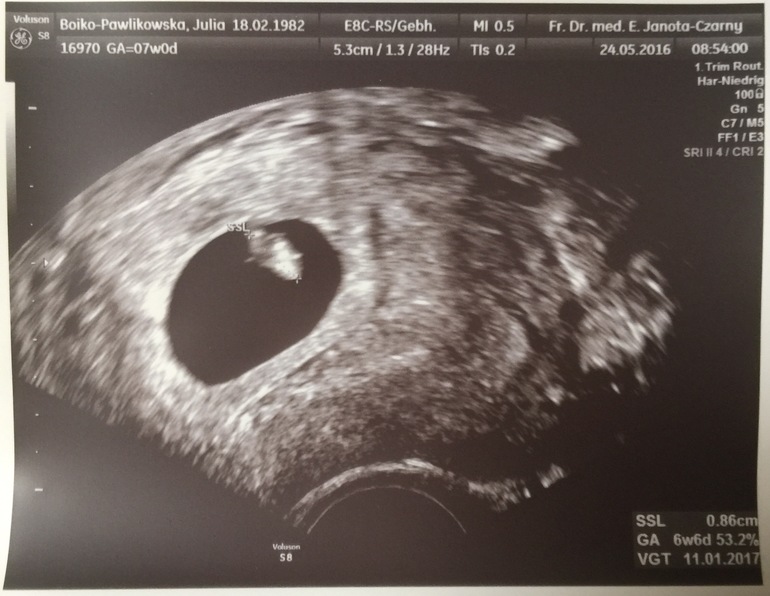

Наше первое узи

Сегодня, 20.05.16 мы первый раз посетили нашего врача .

Сегодня закончилась 7-я неделя . Мне было очень-очень страшно идти к врачу, я так боялась, в голове кружились мысли "а вдруг опять нет эмбриона" , " а если нет сердечка" и т.д., но слава богу узи подтвердило ,что все у моего человечка есть : и сердечко, и тельце 😍😍😍 Мы уже целых 7 мм 😄 Я самая счастливая на свете 😊